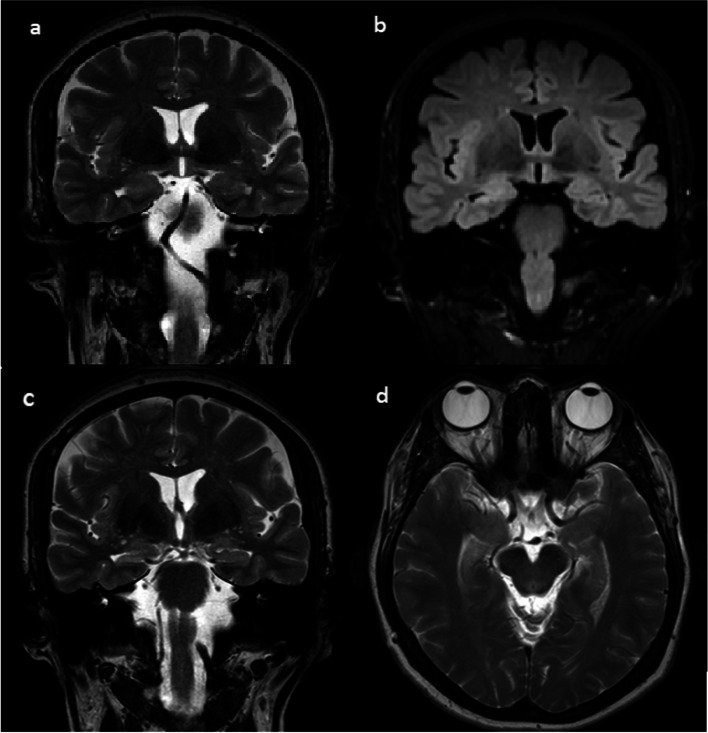

内侧颞叶硬化(MTS)突出作为一个普遍的病因医学难治性颞叶癫痫。了解MTS的病理改变、临床表现和危险因素对认识和怀疑MTS至关重要。在本文中,我们对MTS的病理生理、临床表现和治疗方案进行了全面的综述,目的是提供对这种疾病的最新了解。

Mesial temporal sclerosis (MTS) stands out as a prevalent etiology of medically intractable temporal lobe epilepsy. Understanding the pathological alterations, clinical manifestations and risk factors of MTS is crucial for the recognition and suspicion of this condition. In this paper, we provide a comprehensive narrative review on the pathophysiology, clinical manifestations, and treatment options for MTS. By doing so, we aim to provide an up-to-date understanding of this condition.